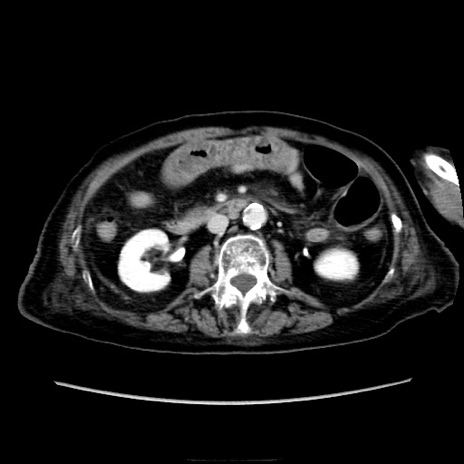

症例40(横断像)

【症例】90歳代女性

【主訴】腹痛・嘔吐

【現病歴】 食欲低下、嘔吐があり昨日他院受診。肺炎と診断され入院となる。入院後より腹部全体に圧痛あり。胃管留置され経過みていたが、症状持続するため、

当院転院となる。

【既往歴】胸椎圧迫骨折、胆石症

【身体所見】腹部:中央に激痛あり、圧痛あり、反跳痛不明

【データ】WBC 17100、CRP 18.82

冠状断像